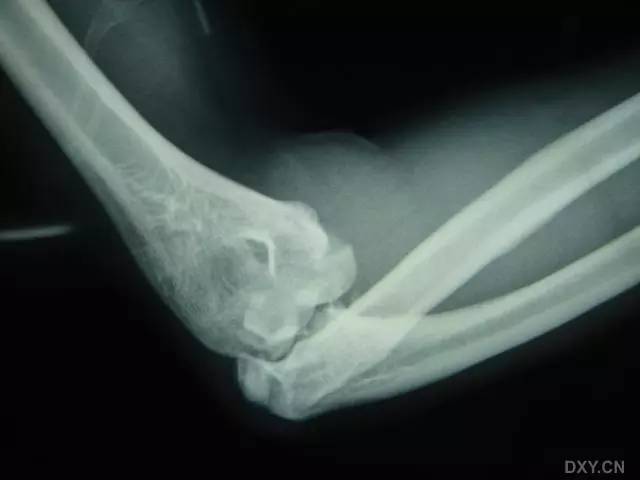

全肱骨小头骨折,为一种少见的关节内骨折,多见于成年人。常由于跌倒时手过度伸直或在屈肘时因桡骨小头撞击肱骨小头,并同时有外翻力存在时发病,亦可伴有滑车骨折与内侧副韧带的撕裂。X 线表现为全肱骨头骨折,向上移位。

Hahn-steinthal 骨折 X 片(来源:Hahn-Steinthal fracture: a case report.BioMed central Cases Journal20081:239)